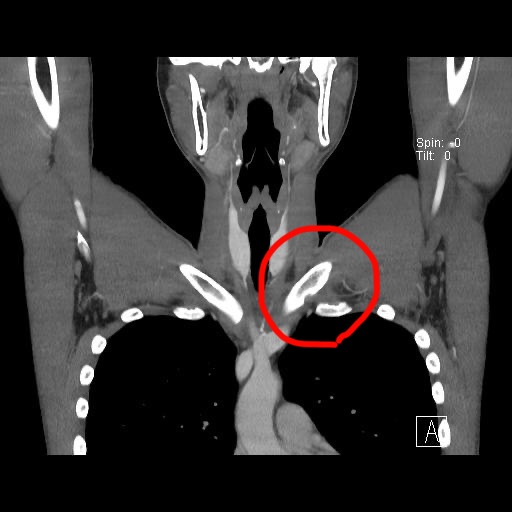

この前ついに京大病院に行ってきたら、鎖骨と肋骨の1番上がぶつかっているらしく、手術するしかないと言われました。どうも信用ならないので、CTの画像をもらってきて自分でも見てみました。

高校の時に撮ってもらったやつなので、今どうなってるかは分かりませんが、確かに左の鎖骨が凹んでます。骨と骨とが当たってるのかは分かりませんでした。姿勢によっては当たってて、削れてきてるとかあるんでしょうか。それやとしたらしたら、痛そうすぎるけど。有識者の方、ぜひ見解をお聞かせください。水泳はまだマシな方で、ちょっとお勉強したりバイト行ったりするだけで肩痛なるんは流石に社会で使いもんにならなさすぎるんで、今んとこ8:2ぐらいで手術しよ思ってます。